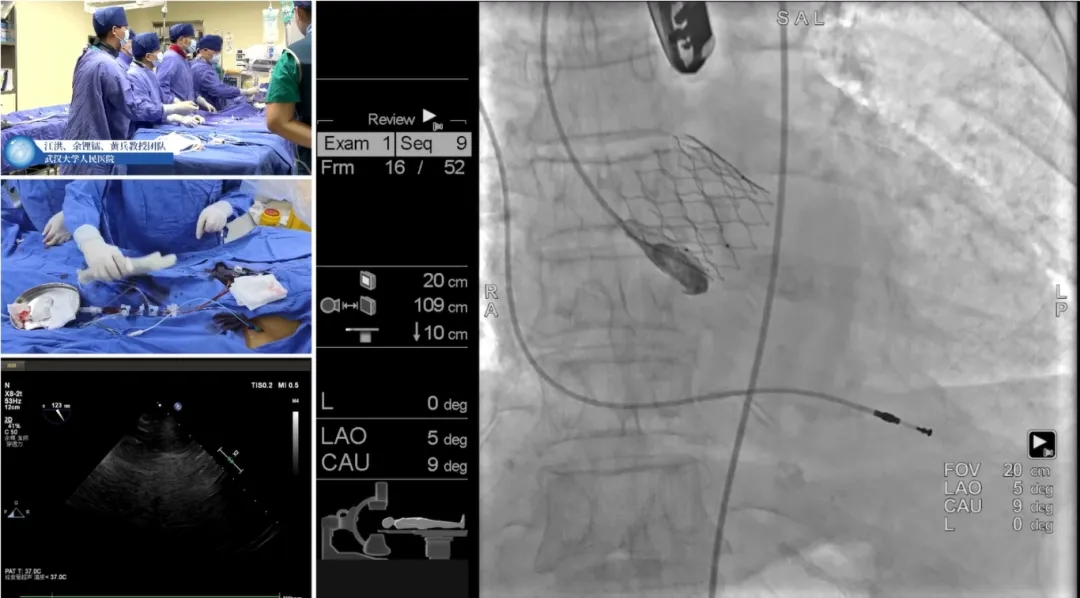

初始造影确定无冠窦

瓣膜释放过程(可见窦部扭转带来的异常轴向)

完全释放瓣膜左右重叠下评估位置

左冠切线位下立体评估左冠深浅

瓣膜脱钩

脱钩后造影

瓣膜无位移

撤出猪尾造影

无窦深约1mm

最终近左冠切线位造影,左窦深约5mm